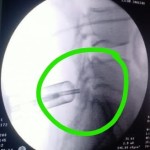

استئصال غضروف قطني بالمنظار